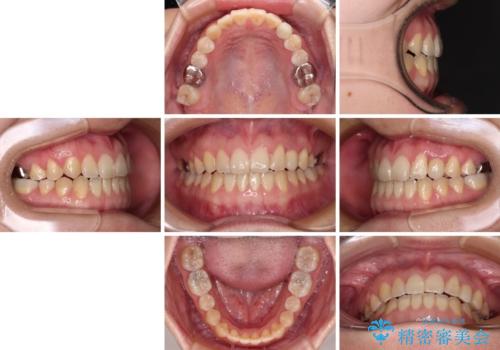

受け口で開咬を急速拡大装置とインビザラインで改善 欠損部分はインプラントにて補綴治療

矯正治療が終わるタイミングに合わせてインプラントの埋入を行っていたので、矯正治療を終了すると同時にセラミック補綴治療を行えました。

インビザラインの装着時間が不十分であったので、治療期間は長期間となりました。